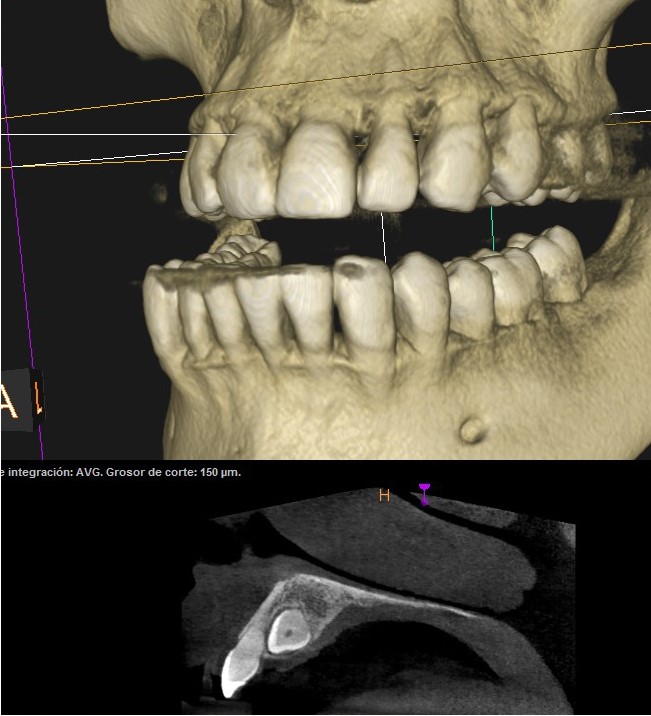

Este método es fundamental para planificar procedimientos como implantes dentales, cirugías maxilofaciales o diagnósticos de patologías dentales complejas. La precisión del TAC Dental 3D permite lograr unos resultados óptimos para cada paciente.

Es necesario en diversas situaciones: cuando se planifican implantes dentales, ya que permite evaluar tanto la densidad ósea como la ubicación exacta del implante; en cirugías maxilofaciales, para obtener una visión detallada de las estructuras implicadas; y en diagnósticos complejos de patologías dentales, como quistes o tumores.

También es útil en casos de traumatismos faciales ya que permite evaluar la anatomía dental en tratamientos de ortodoncia. Esta herramienta avanzada es indispensable para ofrecer tratamientos precisos así como para garantizar la mejor atención para cada paciente.